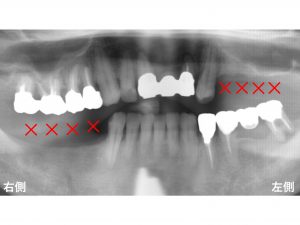

以下が初診時です。

上顎左側の奥歯と

下顎右側の奥歯

が欠損しており、噛めないとのことで来院されました。

上顎左側の奥歯が4歯欠損、

下顎右側の奥歯も4歯欠損しています。